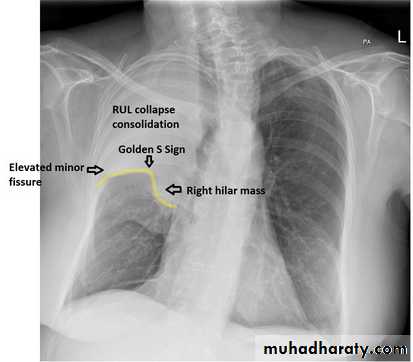

RLL collapse - PA.